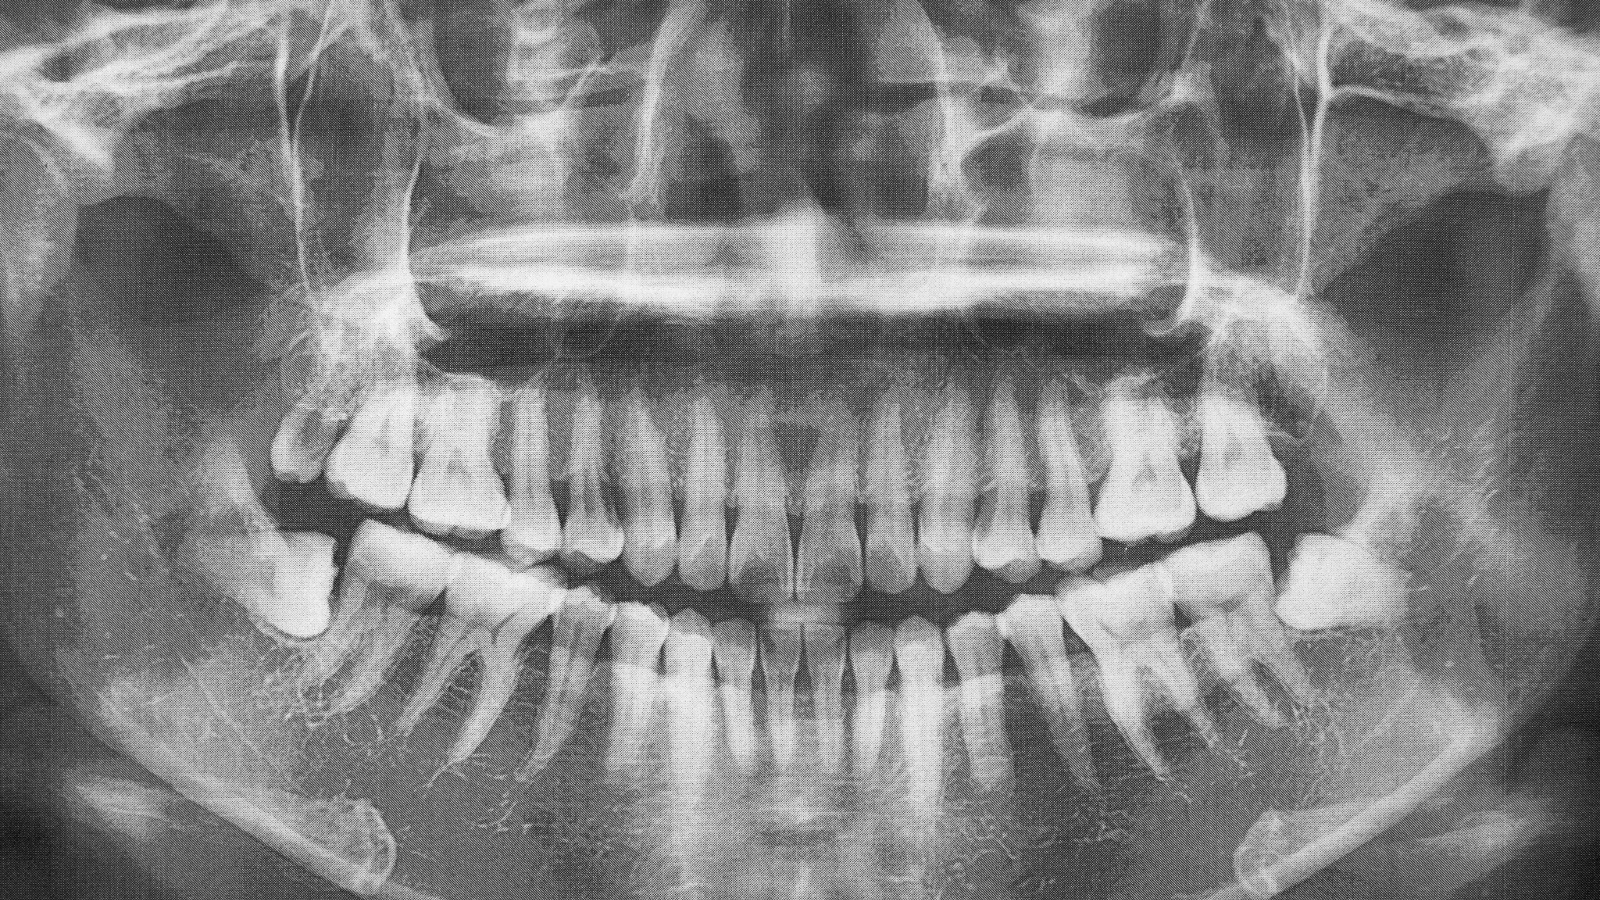

A panoramic X-ray is a two-dimensional dental radiograph that captures the entire mouth in a single image. Also known as an Orthopantomogram (OPG), it shows the upper and lower jaws, all teeth (both erupted and unerupted), the jaw joints (TMJ), and the sinuses. This wide-view imaging allows our dental team to assess oral and maxillofacial structures all at once, without the need for multiple individual X-rays.

A panoramic X-ray gives valuable insight into many aspects of oral and jaw health, including:

- Tooth position and development, including impacted wisdom teeth

- Missing, extra, or unerupted teeth

- Jawbone health and bone levels

- Jaw fractures or signs of trauma

- Cysts, tumors, or infections

- Temporomandibular joint (TMJ) abnormalities

- Sinus issues related to dental structures